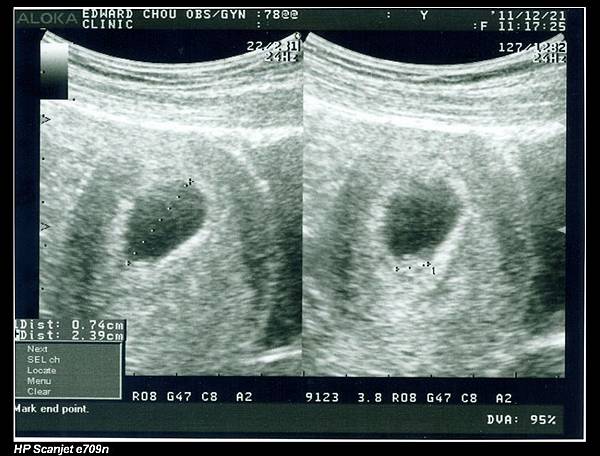

余小龍還很小,七週大,長度才0.74公分卻已有心跳,真是不可思議。

下圖右方就是余小龍的心跳頻率。